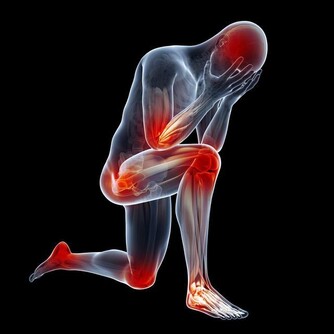

而且,痛風一般都是在夜間發作,在睡前喝點水,能夠預防在長時間的睡眠過程中發生尿酸濃縮,尿酸含量增高。